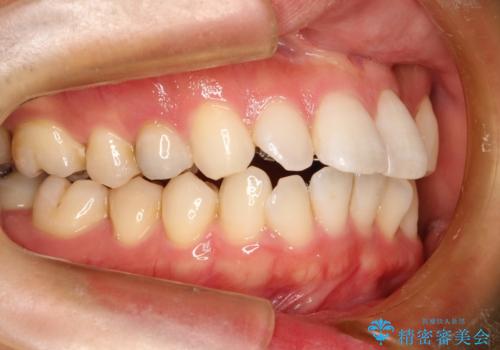

フルリンガル矯正 非抜歯でガタつきを整える

- フルリンガル

- 1年6ヶ月

- フルリンガルワイヤーによる非抜歯治療を計画しました。